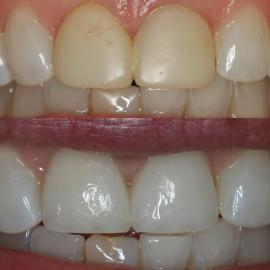

Ceramics can make a smile look nice again

Opening the bite position provides a more stable

position also protecting the front teeth